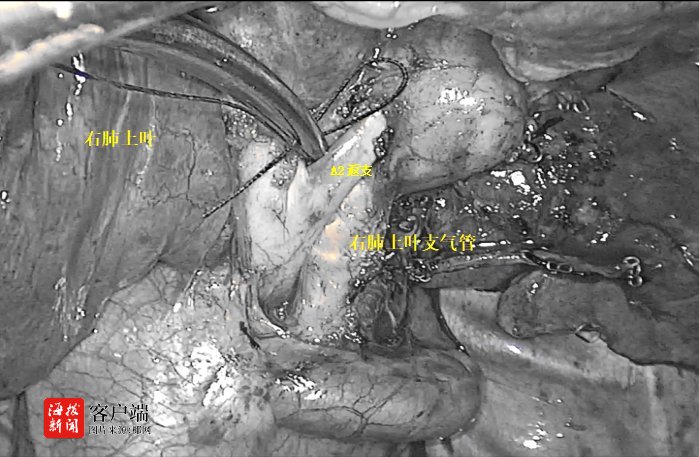

术前,赵主任团队分析肺段动脉、静脉及支气管,并准确定位结节位置,精准分析切除范围,制定肺段切除计划。术中,由于李女士叶间裂发育不全,给后段切除手术造成了一定阻碍,但赵宏光主任凭借着坚实的解剖知识及高超的手术技巧和丰富的手术经验,清晰地将各个结构分离并离断各支肺段动脉、静脉及支气管,精准地切除右上肺后段。

据介绍,目前海医一附院胸外科已行多台单孔胸腔镜下解剖性肺段切除术(包括右肺上叶后段、右肺下叶后段+外基底段亚段、左肺上叶前段、左肺上叶尖后段等)。该术式的成功开展,标志着胸外科手术上升到一个新台阶,技术水平达到国内先进、省内领先水平。